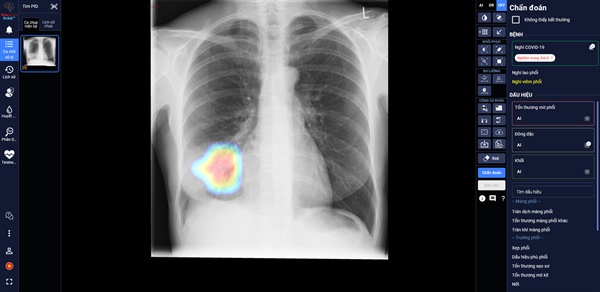

DrAid giúp bác sĩ theo dõi mức độ tổn thương phổi ở một bệnh nhân F0 trên ảnh X-quang phổi

Trong các bệnh viện thu dung điều trị Covid-19, DrAid cho Covid-19 giúp các bác sĩ đánh giá mức độ tổn thương phổi của bệnh nhân Covid-19 qua các ngày, từ đó đưa ra các chỉ định điều trị kịp thời và hiệu quả cho bệnh nhân.

Theo đánh giá của các bác sĩ tại Trung Tâm Y Tế Kỳ Anh – Hà Tĩnh, AI đã giúp đỡ các bác sĩ khá nhiều khi theo dõi tổn thương qua các ngày, nhận diện rõ ràng là tổn thương lan rộng như thế nào. Ngoài ra, AI cũng giúp bác sĩ nhận diện các tổn thương nhỏ dễ bỏ sót.